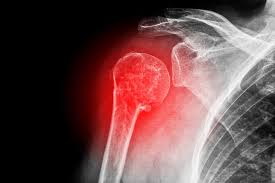

Sakit Dekat Tulang Belikat : Tulang tersebut menghubungkan tulang lengan atas ke tulang selangka.. Tulang belikat sakit dapat terjadi akibat cedera, tendonitis, diseksi aorta, hingga emboli paru. Aktivitas harian seperti untuk mencuci rambut, berpakaian, membuka pintu mobil, meraih gula di lemari saat membuat kopi, anda menggunakan sendi bahu agar dapat melakukannya semua. Sakit urat belikat atau lebih dikenali sebagai scapulocostal syndrome adalah sejenis penyakit yang berkaitan dengan otot dan sendi. Selain itu, anda juga tidak bisa melakukan gerakan gerakan seperti mengangkat tangan pada sisi tulang belikat yang patah. Tulang belikat adalah tulang segitiga yang terletak di bagian belakang bahu atau punggung bagian atas.

Sakit tulang belikat adalah rasa sakit pada tulang bahu yang penyebabnya tidak selalu diketahui secara pasti. Dalam beberapa kasus, nyeri tulang belikat disebabkan oleh rasa sakit dari organ terdekat yang sedang tertekan. Strukturnya yang kompleks membuat tulang satu ini rentan terhadap cedera yang dapat menimbulkan sakit bahu. Aktivitas harian seperti untuk mencuci rambut, berpakaian, membuka pintu mobil, meraih gula di lemari saat membuat kopi, anda menggunakan sendi bahu agar dapat melakukannya semua. Ia seringkali melibatkan kawasan bahagian tulang belikat, bahagian belakang bahu dan boleh merebak ke bahagian tengkuk dan menimbulkan ketidakselesaan pada pesakit. Apabila bahagian bahu tegang, maka ia akan menyekat pergerakan leher. Bahu adalah bahagian yang penting untuk diurut. Misalnya pada pasien yang telah mengalami operasi pengangkatan payudara.

Nyeri tulang belikat bisa diatasi secara mandiri dengan beberapa cara berikut ini: Belikat adalah tulang berbentuk segitiga di bagian belakang bahu atau punggung atas dan bernama lain tulang scapula (shoulder blade). Sebenarnya banyak faktor yang bisa menjadi pemicu dan penyebab terjadinya sakit pada tulang belikat. Iaitu leher akan terasa sakit apabila toleh ke kanan dan ke kiri. Biasanya, nyeri tulang belikat tidak sesederhana nyeri yang berhubungan dengan cedera. Sebagai contoh, sakit tangan, sakit leher, sukar untuk bernafas dan sakit bahu. Terkadang seseorang mengalami sakit pada bagian ini sehingga dibutuhkan pijat sakit belikat. Herniasi diskus di tulang belakang leher bagian bawah lebih mungkin untuk memancarkan rasa sakit ke atau dekat area tulang belikat. Jika rasa sakit pada tulang belikat disertai dengan beberapa gejala di atas. 9 obat untuk sakit tulang belikat secara alami yang aman dikonsumsi. Ada masanya kesakitan itu tidak sangat terasa dan saya boleh menjalankan rutin harian seperti biasa. If you have question you can message me contact instagram : Gejala umum cedera tulang selangka antara lain:

Anda perlu segera menghubungi dokter apabila tulang belikat sakit parah, tidak normal, dan tidak hilang setelah beberapa minggu. Rasa sakit yang pada belikat biasnya akan hilang dalam sendirinya dalam berapa hari kedepan namun ada beberapa metode untuk menghilangkan rasa sakit pada belikat agar cepat menghilang, berikut kami. Metode menghilangkan rasa sakit pada belikat. Tulang tersebut menghubungkan tulang lengan atas ke tulang selangka. Iaitu leher akan terasa sakit apabila toleh ke kanan dan ke kiri. Istirahat yang cukup dapat mempercepat proses pemulihan. Bahu adalah bahagian yang penting untuk diurut. Nyeri tulang belikat dapat terasa tajam atau terbakar pada area antara tulang belakang dan tulang belikat.

Kondisi tersebut biasa didahului dengan adanya trauma/cedera. Patah tulang, rasa sakit pada belikat juga bisa di karenakan anda mengalami patah tulang belikat. Tulang tersebut menghubungkan tulang lengan atas ke tulang selangka. Sakit tulang belakang berdampak hingga tidak bisa berjalan. Dalam mengatasinya, anda bisa meletakkan kompres es, latihan fisik, peregangan, atau konsumsi obat pereda nyeri. Tulang belikat atau skapula adalah tulang berbentuk segitiga di punggung bagian atas. Terkadang seseorang mengalami sakit pada bagian ini sehingga dibutuhkan pijat sakit belikat. Belikat adalah tulang berbentuk segitiga di bagian belakang bahu atau punggung atas dan bernama lain tulang scapula (shoulder blade). Selain itu, anda juga tidak bisa melakukan gerakan gerakan seperti mengangkat tangan pada sisi tulang belikat yang patah. Gejala umum cedera tulang selangka antara lain: Saya mengalami sakit bagian punggung dekat tulang belikat. Tidak menutup kemungkinan rasa sakit itu muncul sebagai gejala dari kondisi kesehatan serius. Tulang belikat adalah tulang berbentuk segitiga yang berada di bagian atas punggung.

Titik pijat sakit tulang belikat. Apa yang harus saya lakukan dok. Iaitu leher akan terasa sakit apabila toleh ke kanan dan ke kiri. Penyebab nyeri tulang belikat dislokasi tulang rusuk meskipun kurang umum, tulang rusuk dapat keluar dari tempatnya atau menjadi tidak sejajar setelah tekanan berulang. Operasi dapat menyebabkan rasa sakit pada tulang belikat. Rasa sakit karena diseksi aorta dapat menyebabkan nyeri bahu yang tajam. Sakit tulang belakang berdampak hingga tidak bisa berjalan. Saya mengalami sakit bagian punggung dekat tulang belikat. Apabila bahagian bahu tegang, maka ia akan menyekat pergerakan leher. 9 obat untuk sakit tulang belikat secara alami yang aman dikonsumsi. Aktivitas harian seperti untuk mencuci rambut, berpakaian, membuka pintu mobil, meraih gula di lemari saat membuat kopi, anda menggunakan sendi bahu agar dapat melakukannya semua. Tulang belikat atau skapula adalah tulang berbentuk segitiga di punggung bagian atas. Tulang ini memiliki peranan penting untuk tubuh, salah satunya adalah menstabilkan gerakan bahu.